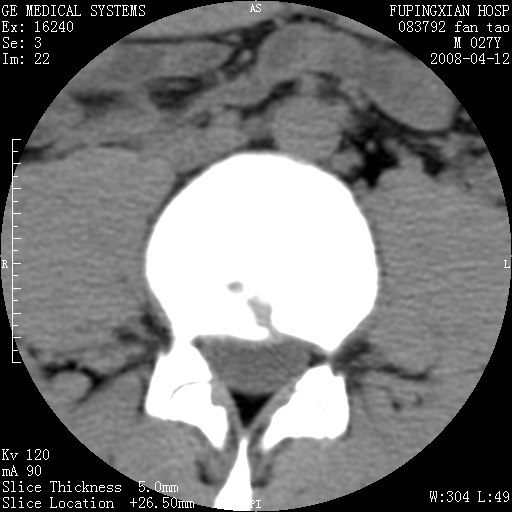

以下是引用前行在2008-4-13 13:53:00的发言:[br]椎间盘髓核终板下突出形成许莫氏结节及椎间盘突出,建议mr检查

以下是引用xclzq_910在2008-4-13 12:43:00的发言:[br]这个应该没什么了,椎间盘突出后反应性骨质吸收硬化.建议mr